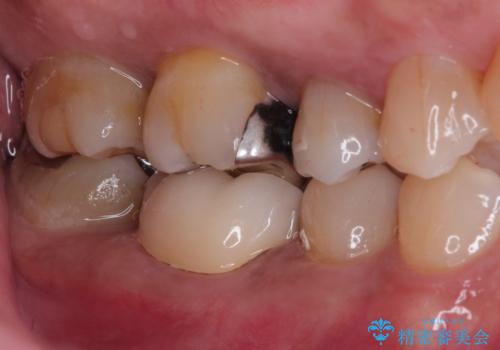

奥歯が痛い。精密根管治療〜オールセラミッククラウン

歯髄診断と痛みの再現により原因歯を特定し、症候性不可逆性歯髄炎の診断となりました。

根管治療〜オールセラミッククラウン(エクセレント)の治療を行なっております。

根管治療後の最終補綴物は予後に大きく関わります。